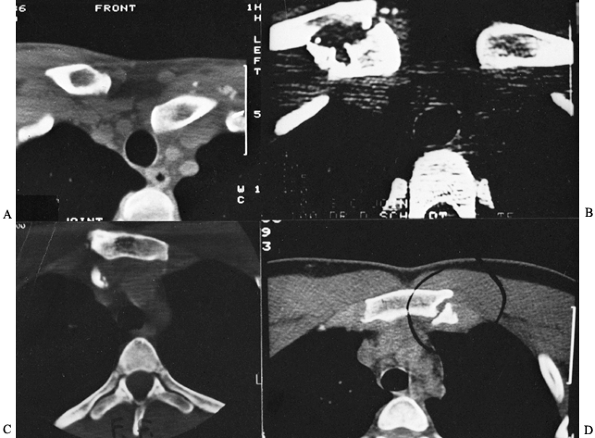

It clearly distinguishes injuries of the joint from fractures of the

medial clavicle and defines minor subluxations of the joint.

| Figure 78.29. Computed tomography scans of the SC joint demonstrating various types of injuries. A: Posterior dislocation of the left clavicle compressing the great vessels and producing swelling of the left arm. B: Fracture of the medial clavicle that does not involve the articular surface. C: Fragment of bone displaced posteriorly into the great vessel. D: Fracture of the medial clavicle into the SC joint. (Reprinted with permission from Rockwood CA, Matsen F III, eds. The Shoulder. Philadelphia: WB Saunders.) |